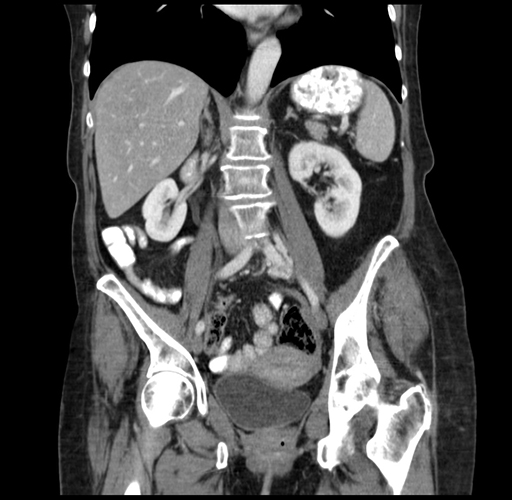

Pre-Chemo: Coronal Venous

Coronal Venous